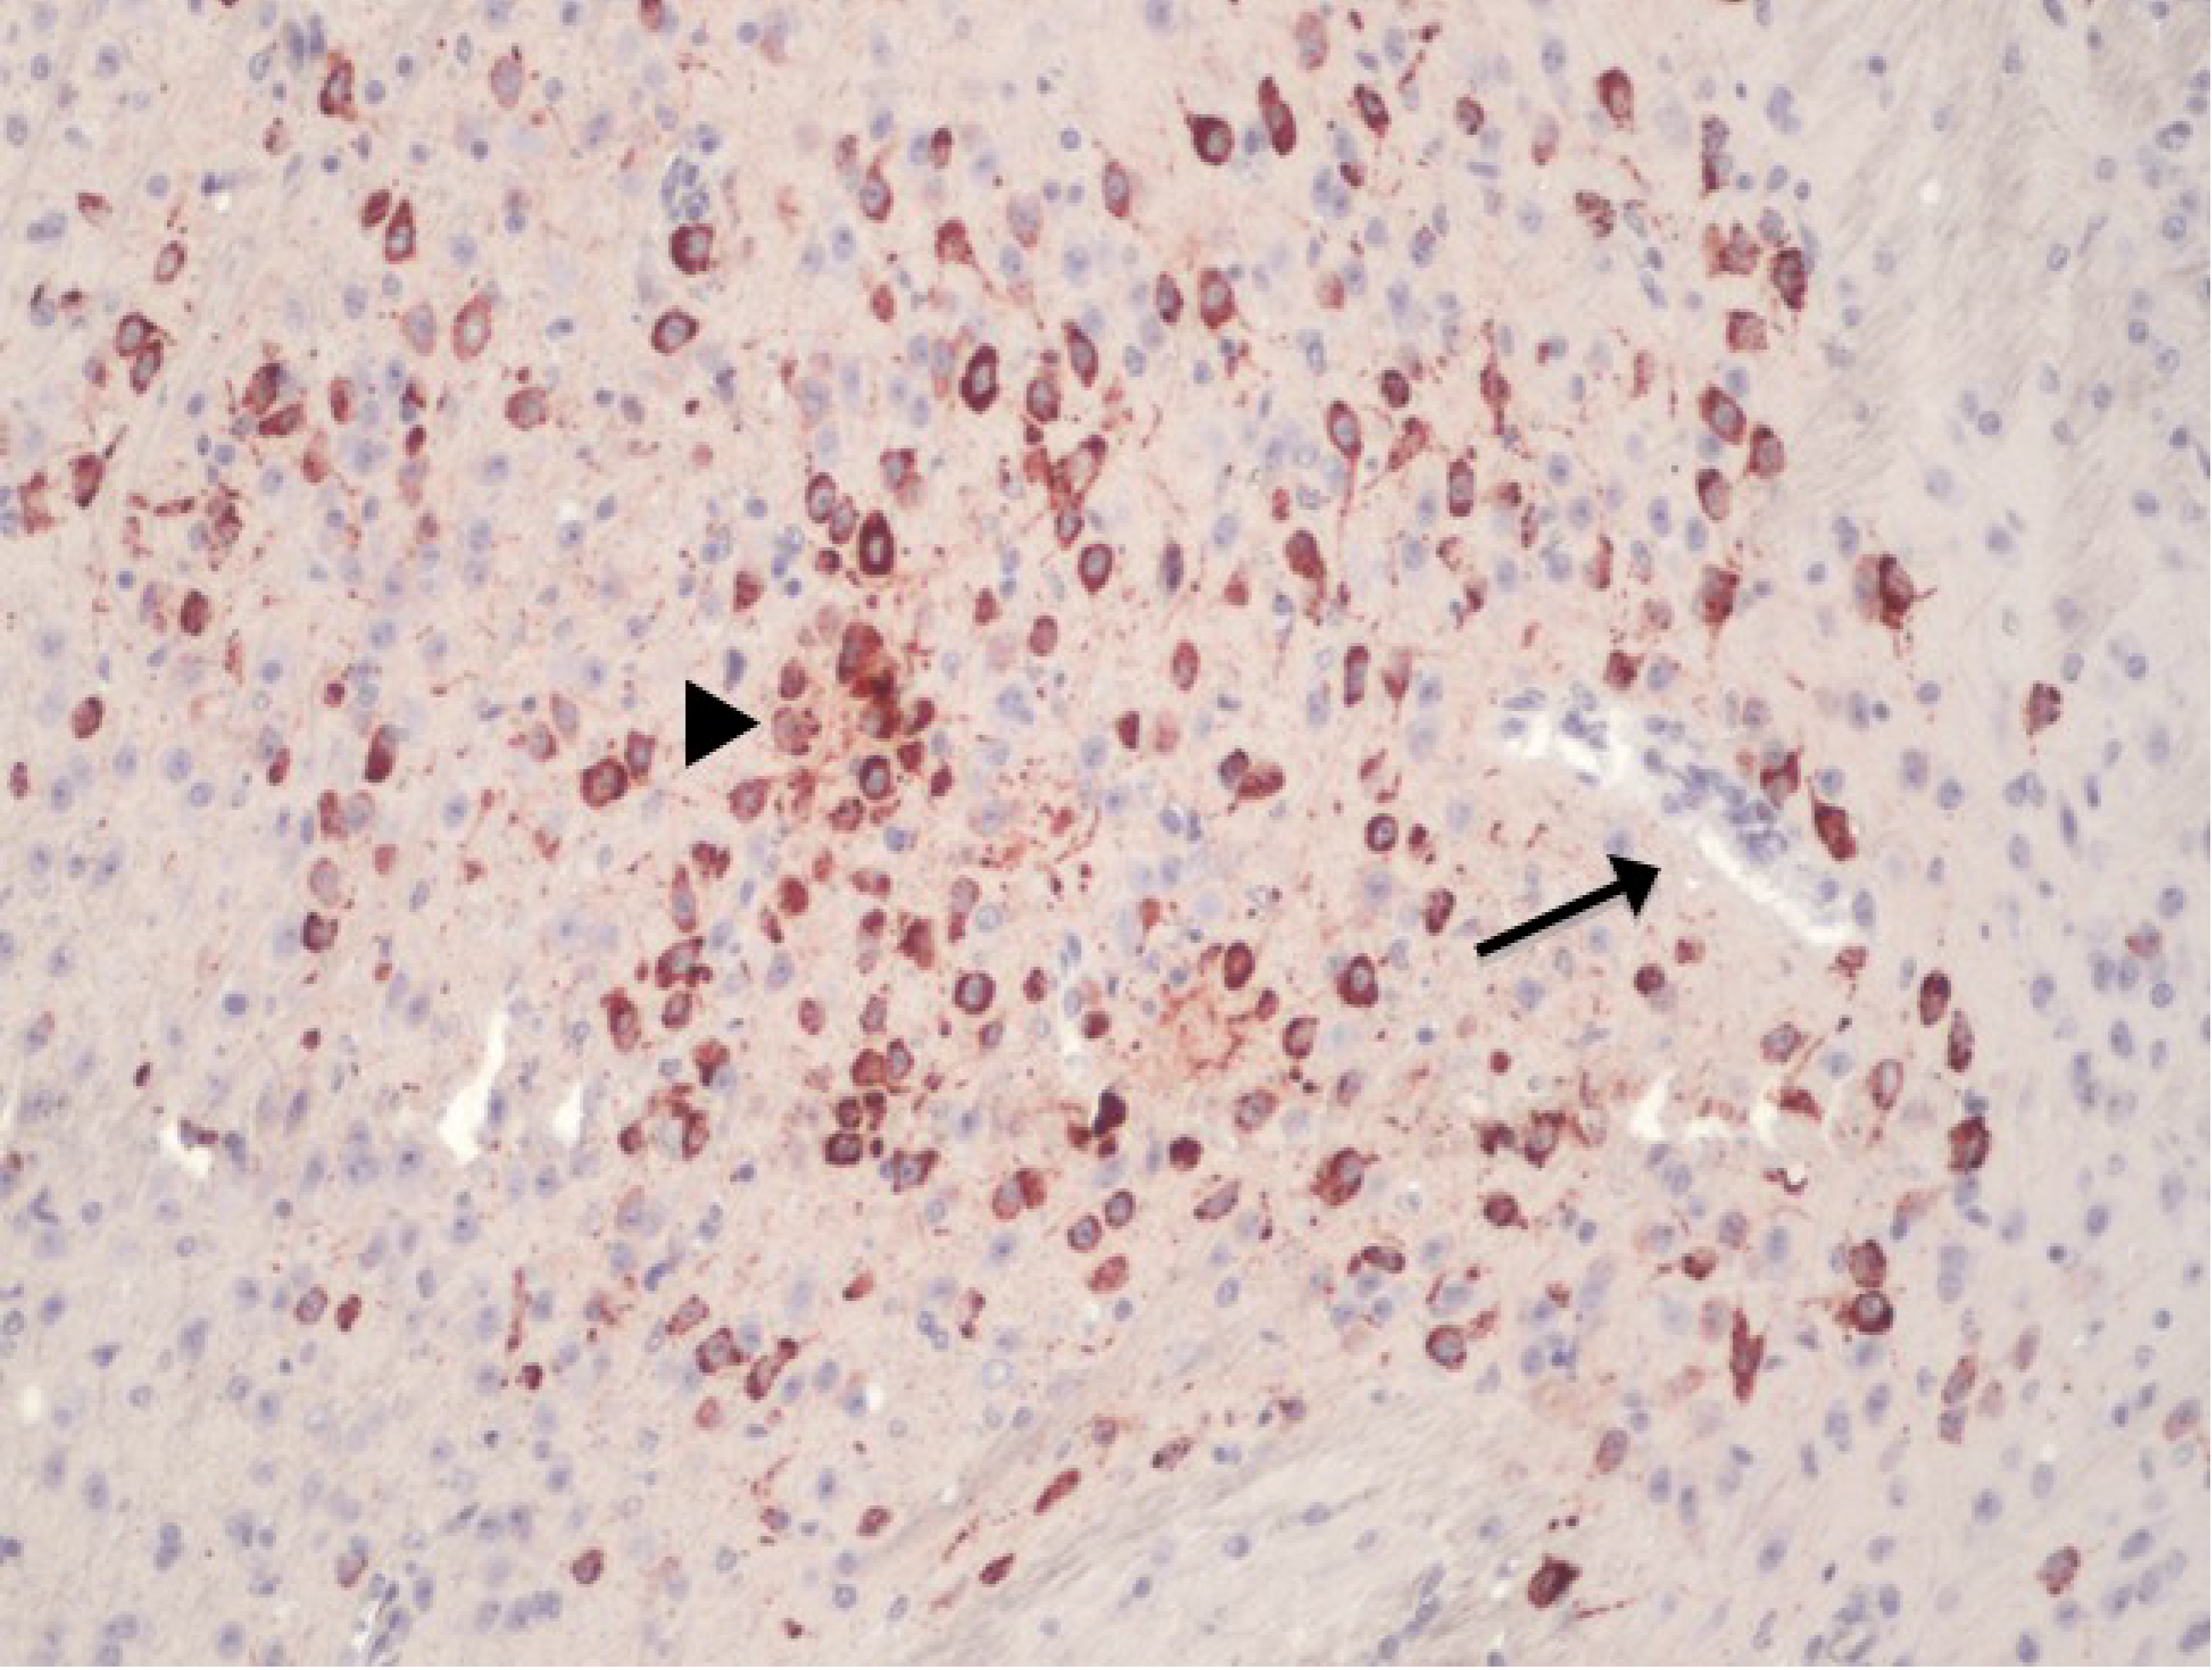

However, as observed by Hasebe et al. [33] and Dropulic and Master [35], the ability of virus to infect endothelial cells could be virus species specific and could even be strain specific. Furthermore, in vivo evidence of endothelial cell infection is lacking. One human case report noted the presence of JEV antigen in the endothelial cells of infected brains by immunohistochemical labeling [36]. However, on closer examination of the referred microphotomicrograph, the stained focus did not appear to be located in the endothelial cells, but was adjacent to it [36]. Indeed, brain endothelial cell infection by WNV can be absent even in the face of pronounced neuronal infection in mice (Figure 1). More importantly, brain endothelial cell infection is not a feature of WNV infection in the common target host, the equids [37]. This illustrates that the behaviour of in vitro grown endothelial cells can be quite different to that seen in vivo, especially when endothelial cells were cultured alone, as was the case in the studies by Verma et al. [32] and Hasebe et al. [33]. Therefore, the transcellular passage hypothesis suggested for WNV neuroinvasion requires further validation in an appropriate in vivo model.

Figure 1. Immunohistochemical labelling with anti-flavivirus NS1 monoclonal on brain section from a Swiss CD1 mouse, infected with an Australian West Nile virus (WNV) subtype, WNVKUN. Despite ample neuronal infection (red stain, arrowhead), the endothelial cells are not infected (arrow). (Antibody binding was visualized using AEC substrate and the section counterstained with Mayer’s hematoxylin; magnification at 400×).